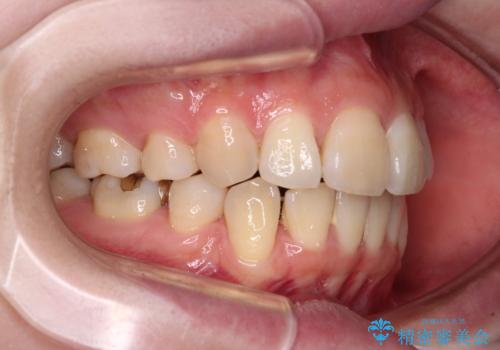

- 奥歯の欠損と、抜歯矯正の後戻りを気にして来院された患者様です。

上下前歯をワイヤー保定していましたが、強い舌の突出癖により上下ともにスペースができ、上下前歯は非接触になっていました。

また、上顎臼歯は虫歯により抜歯されてから放置されている状態でした。

舌のトレーニングをしっかりと行っていただきながらワイヤー装置により矯正治療を行い、途中でインプラントを埋入し、矯正治療後に補綴治療を行うこととしました。